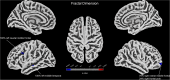

Results: Compared to participants in the PWH control group, those in the PWH-DD group showed higher scores in evaluation of depression, anxiety, sleep disturbances, childhood trauma, and mental health symptoms, indicating a greater burden of psychological and emotional distress. Comparisons of brain structure showed that participants in the PWH-DD group exhibited lower GMV in the left middle frontal gyrus, shallower sulcal depth in the left supramarginal and bilateral superior parietal regions, and lower fractal dimension in multiple frontal and temporal lobe areas compared to those in the PWH control group. Among all participants, correlation analysis demonstrated that GMV of the left middle frontal gyrus was significantly negatively correlated with Self-Rating Depression Scale scores.